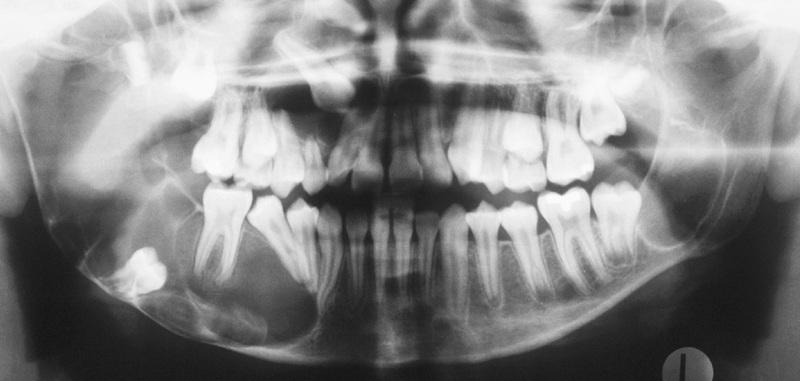

Large cysts present in the right and left mandibular molar regions, together with a smaller cyst involving the right maxillary canine.

nevoid basal cell carcinoma syndrome